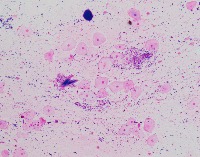

Medical Image Analysis: geckler3 could be used by healthcare professionals, researchers, and medical students to quickly and accurately identify White Blood Cells (WBC) and Erythrocyte-Hemoglobin Concentration (EHC) in clinical images, improving diagnosis and understanding of various blood-related conditions and diseases.

Blood Disorder Diagnosis Support: Implement geckler3 in diagnostic tools to assist doctors in identifying blood disorders, such as anemia or leukemia, by accurately analyzing WBC and EHC levels in blood images, helping with faster and precise diagnosis and treatment.

Biomedical Research: Utilize geckler3 in research laboratories for various biomedical and biotechnological studies to analyze large datasets of blood images, streamlining the process of data collection and analysis by automatically detecting WBC and EHC patterns.

Training and Educational Tool: Integrate geckler3 into educational platforms or applications to help medical and laboratory professionals, as well as medical students, learn and practice the identification of WBC and EHC in blood images, enhancing their skills and knowledge.

Remote Diagnosis Assistance: Employ geckler3 in telemedicine applications, allowing healthcare professionals to remotely access and analyze blood images for the presence of WBC and EHC, aiding in the diagnosis and management of blood-related conditions in areas with limited medical facilities.